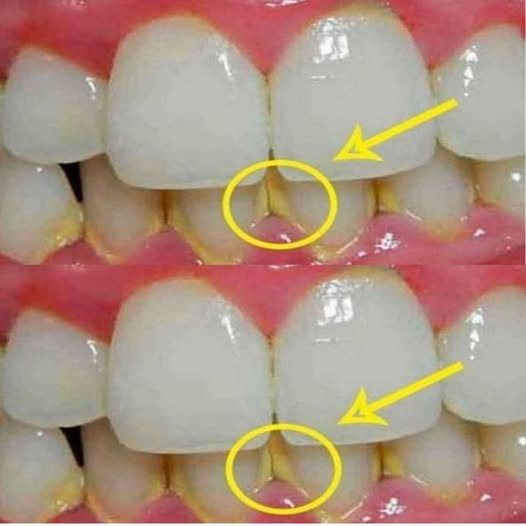

Plaque is a deposit of bacteria, sugars, and acids that naturally forms on the surface of teeth. If not properly removed, it can harden and turn into tartar, making it more difficult to remove and often requiring a trip to the dentist. Poor oral hygiene can lead to problems like bad breath, cavities, and inflamed gums. Fortunately, there are natural remedies to prevent and remove plaque at home.

Plaque buildup is not just a cosmetic issue. If left untreated, it can lead to more serious problems, including:

Tooth decay: The acids produced by plaque bacteria attack tooth enamel, which can cause cavities.

Gingivitis: An inflammation of the gums that can develop into periodontitis if left untreated.

Tooth stains: Plaque can turn teeth yellow or brown over time.